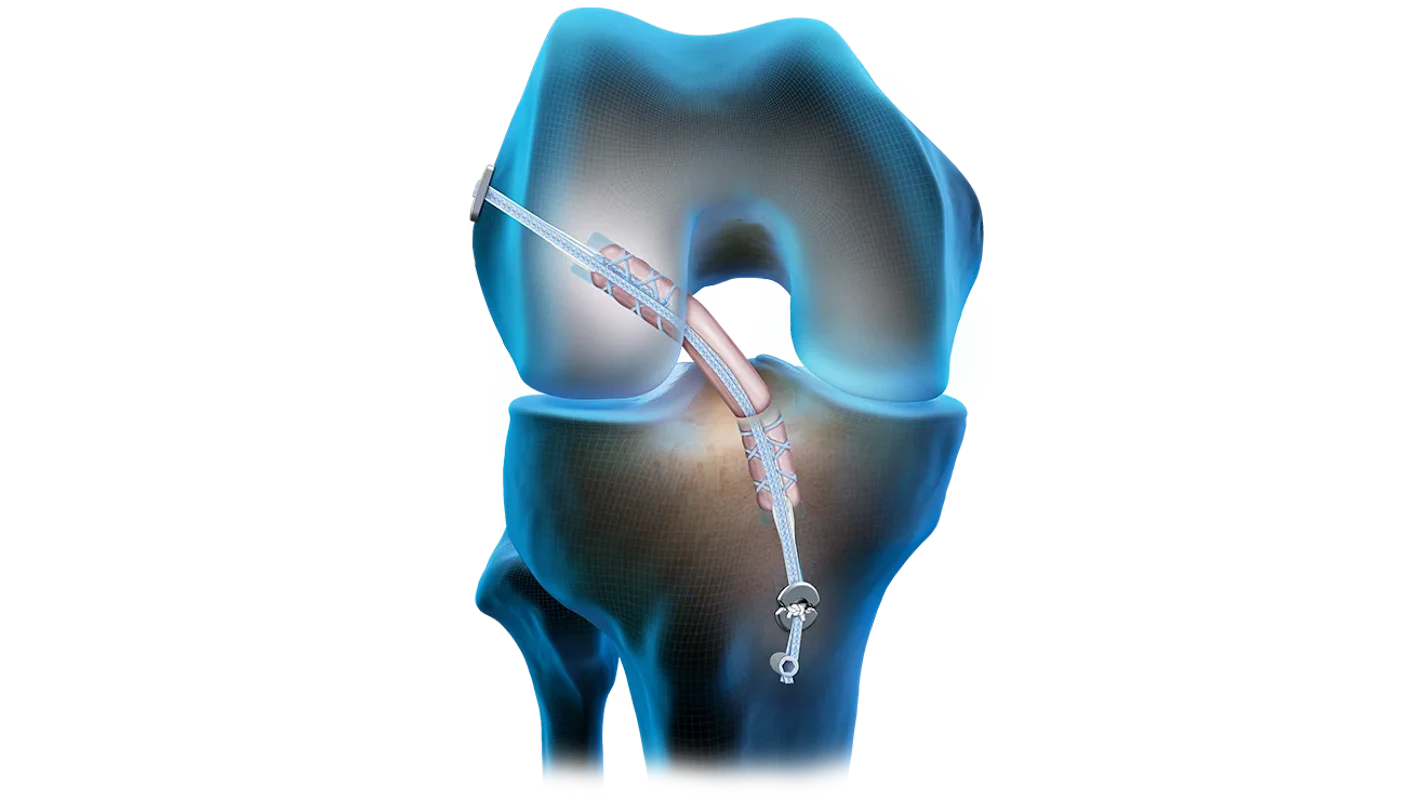

- Implantes para reconstrucción de LCA/LCP

- Reconstrucción multiligamentaria